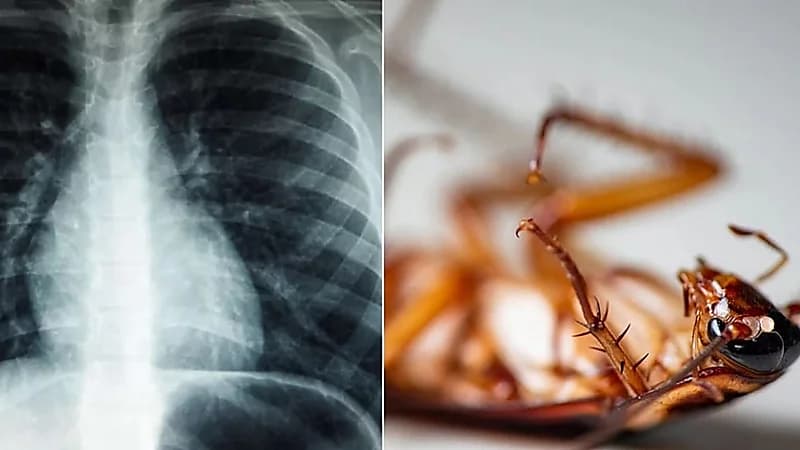

بطول 4 سم .. استخراج صرصور عاش في رئة رجل هندي

في واقعة غريبة من نوعها ، عثر الأطباء في أحد المستشفيات الهندية على صرصور طوله 4 سم داخل رئة رجل ، بعدما اشتكى من مشاكل بالتنفس .

وخضع المريض إلى تنظير للقصبات الهوائية والتي كشفت عن وجود صرصور بطول 4 سم في رئتيه .

وقام الفريق الطبي بإزالة الصرصور من رئة الرجل بعد 8 ساعات من توقف التنفس .

وزعم الأطباء أن الحشرة دخلت إلى رئة الرجل عن طريق أنبوب تم ثقبه في رقبته لتزويده بالأكسجين .